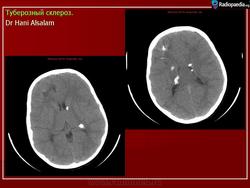

Туберозный склероз (болезнь Бурневилля-Прингла, синдром Бурневилля - Брессау) - глиоз белого вещества мозга, проявляющийся в раннем детстве эпилептическими припадками (в 85%), олигофренией в сочетании с нараста­ющей пирамидной и экстрапирамидной симптоматикой, кожной патологией. В возрасте 4-6 лет на лице в форме бабочки в области носа обычно появляют­ся множественные желто-розовые или коричнево-красные узелки диаметром чуть больше 1 мм - аденомы Прингла, которые обычно признаются аденомами сальных желез, однако есть мнение и о том, что они представляют собой про­исходящую из нервных элементов кожи гамартрому.

На поверхности мозга наблюдаются единичные или множественные глиома-тозные узлы, по цвету несколько светлее окружающего мозга и плотнее его на ошупь, возможна их кальцификация. Узлы могут быть и в белом веществе, под­корковых ганглиях, а также в стволе мозга и в мозжечке.

Встречаются и аномалии развития извилин мозга в виде микро- и пахигирии. Заболевание чаще носит спорадический характер. Бляшки достигают диаметра 5-20 мм. В коре больших полушарий и мозжечка иногда могут быть обнару­жены пластинчатые тельца, напоминающие амилоид. Происходит дегенерация клеток коры. При КТ-исследовании головы нередко можно выявить кальцифика-ты и глиальные узелки в паравентрикулярной области, субэпендимарно вдоль на­ружных стенок боковых желудочков, в зоне межжелудочкового отверстия Мон­ро, реже - в мозговой паренхиме. На М РТ головного мозга в 60% выявляются гипотеденсивные очаги в одной или обеих затылочных долях, которые расце­ниваются как участки неправильной миелинизации (Козлов А.В., 2002).